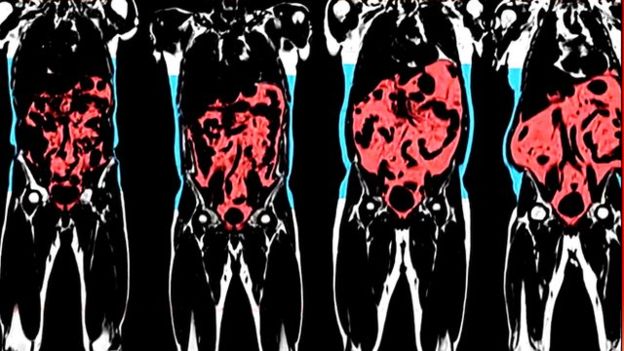

因为,外表苗条的人很可能体内堆积大量脂肪,这些内脏脂肪(visceral fat)通常聚集在心脏、肝脏和胰脏周围。

过多内脏脂肪会增加糖尿病、心脏病和高血压的风险。

研究人员发现,一些BMI正常,体型苗条者有可能内脏脂肪过高。相反,一些BMI偏高,体型微胖者也可能很健康。

测试还显示,两个BMI完全相同者,例如BMI同为21的两个人,一个人内脏脂肪高达6.9升,另一人则为0.7升,区别巨大。

瑞典健康机构Amra的负责人托米·约翰逊(Tommy Johansson)认为在衡量内脏脂肪方面,BMI作用很小。

他说,"这些人看上去是一样的,但一些人可能需要看医生,另外一些则很健康。"